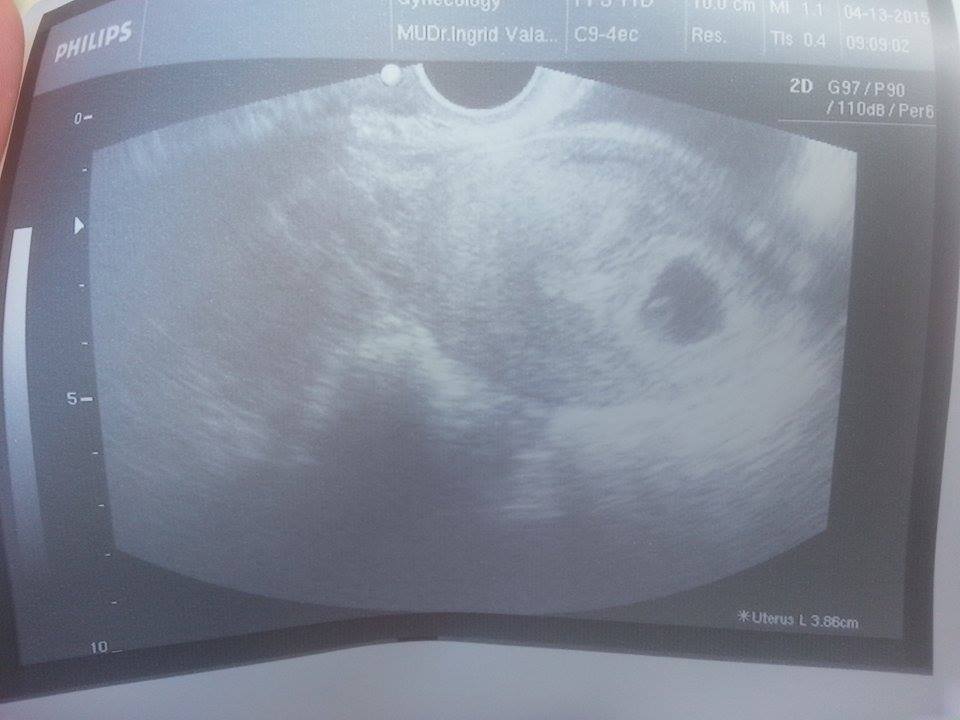

@mirabellka8

a pozerám, že aká kreatívna fotka 🙂

si odfotila monitor tuším 😉

@lucinka3289 bola som 4t+3 a nevidel skoro nič. ešte by som počkala chodí sa tak po 6 týždni, niektoré sa ale ponáhľajú aby mali dôkaz. srdiečko nám ešte nebolo vidieť to až o dva týždne uvidíme

@petra212 nieeee fotila som vytlačenú fotku

@mirabellka8 to fakt? vyzerá to ako fotka monitoru 😀

aj tak je to krásne 🙂